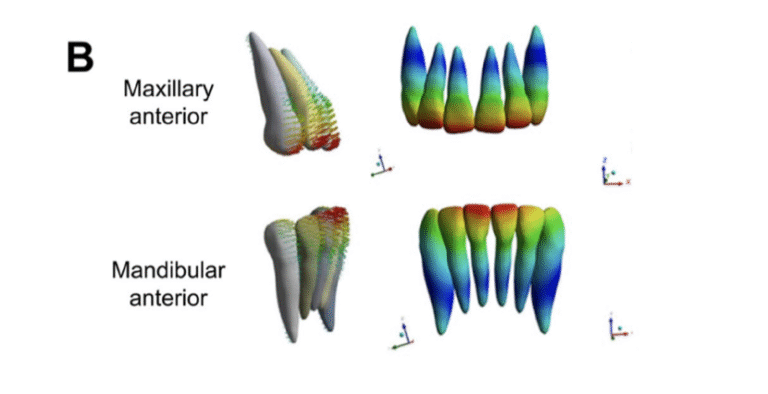

Empezemos por lo que ya sabíamos: una intrusión pura de 2mm es relativamente sencilla de conseguir con alineadores, siempre que la secuencia sea buena y el sistema de anclaje en ataches resulte eficiente.

A partir de ahí, para intrusiones mayores de 2mm… pues resulta más complejo, igual que en ortodoncia fija, cuando podemos emplear por ejemplo arcos de curva reversa.

Por eso nosotros en sistema de biomecánica avanzada nos enfocamos en la posición final del incisivos respecto de sus bases óseas y, si bien intentamos minimizar siempre los movimientos de vaivén, asumimos que pueden ser necesarios para conseguir valores de intrusión mayores de 2mm.